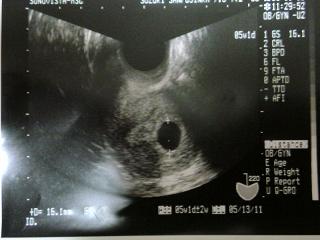

48日目胎のう確認。